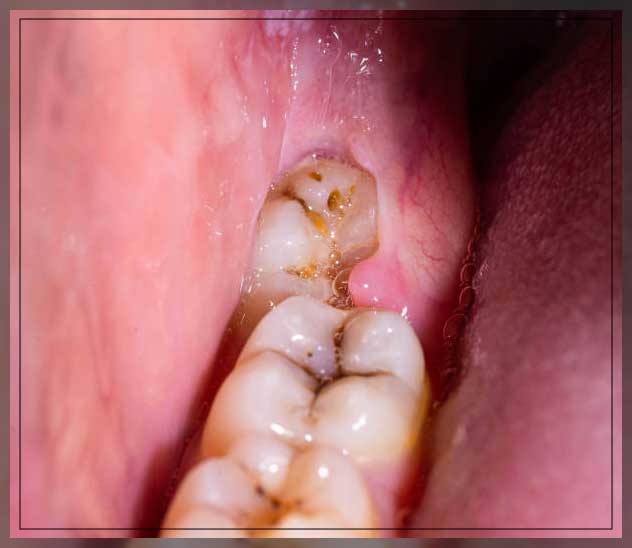

2. Pericoronitis Due to Wisdom Tooth Pain

Gum pain and infection around your wisdom teeth are called pericoronitis. When your wisdom tooth erupts even partially, it may be vulnerable to pericoronitis.

Pericoronitis is primarily defined as gum pain and infection in 6 percent to 10 percent of erupted wisdom teeth. Usually, when your wisdom teeth erupt naturally, this does not create a problem. This disease is commonly observed in teeth that have slowly emerged from the gum line. You can notice the symptom in the lower wisdom tooth.

Pericoronitis can be either chronic or acute. Acute cases may cause severe pain that radiates into nearby areas in your mouth. It may lead to swelling, swollen lymph nodes, tightness in your jaw, difficulty in swallowing, jaw pain, and difficulty while sleeping.

Chronic cases could be more serious and provoke dull pain that may continue for months. Sometimes pregnancy and exhaustion may cause chronic pericoronitis pain to reoccur. Studies have shown that 35 percent to 45 percent of patients with pericoronitis often suffer from a respiratory infection.